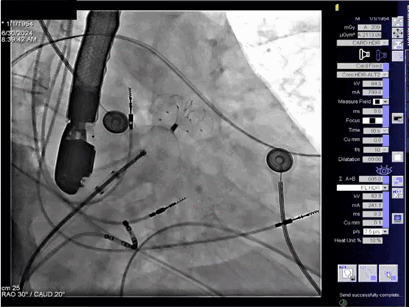

▲牵拉稳定,释放后再观察

于是术者逆时针旋转钢缆,顺利释放封堵器。结合TEE观察到无残余分流,未影响周围组织且无术后心包积液。一次完成封堵,手术很成功。